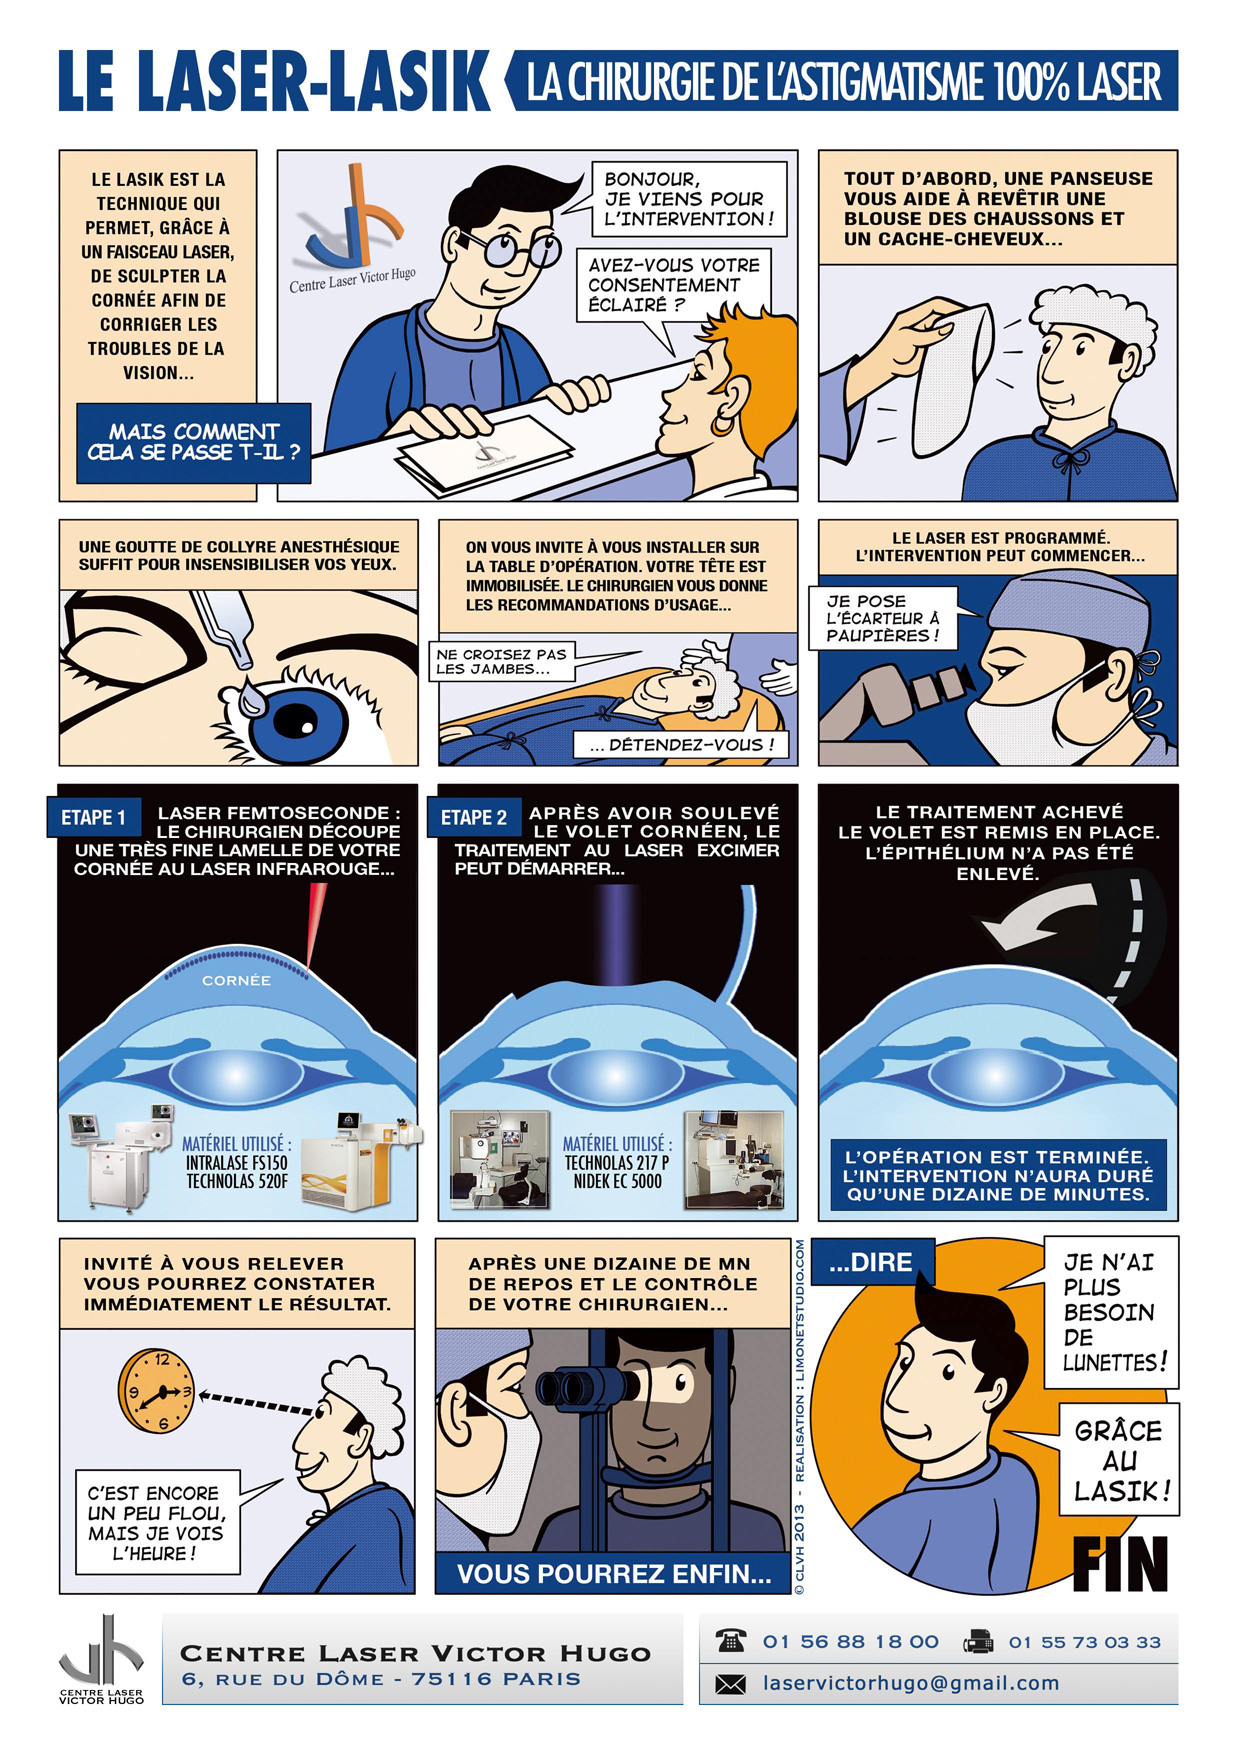

Afin de répondre aux interrogations d'un public de plus en plus intéressé, nous vous proposons cet ouvrage explicatif sous la forme d'une bande dessinée ludique. Cette bédé aborde les troubles de la vision, la chirurgie réfractive (LASIK, PKR et PresbyLASIK), la technique des anneaux et des implants. Cette bébé aborde également l'amblyopie et son traitement orthoptique. Maintenant... à vous de voir !